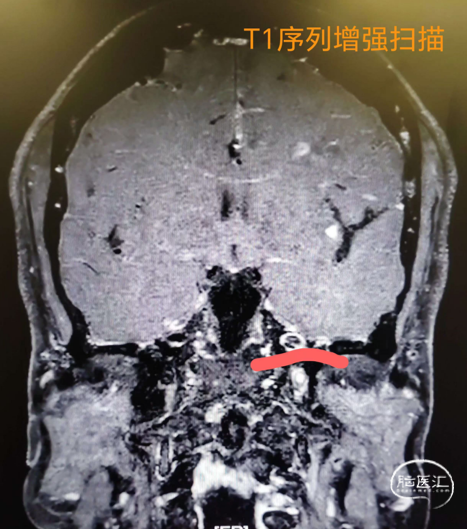

入院颈内动脉颅内段高分辨核磁(2024-09-11)。

入院颈内动脉颅内段高分辨核磁(2024-09-12)。